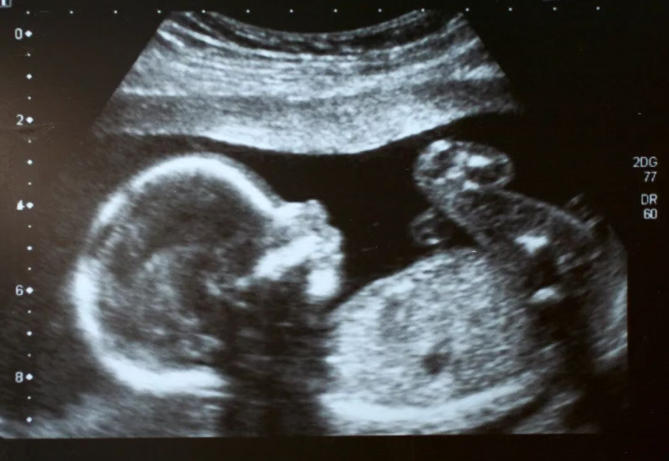

NT(颈项透明层)检查是孕早期一项重要的超声筛查,通常在孕11周~13周+6天进行。

它主要通过测量胎儿颈后透明层的厚度,并结合其他指标(包括鼻骨是否可见等),来评估胎儿是否存在某些染色体异常或结构问题的风险。

鼻骨是鼻梁的支撑骨骼,在超声图像上表现为一条明亮的短线。有时因为以下原因,可能导致暂时“未显示”: